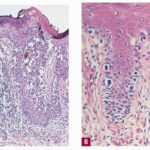

Clinically, in situ or microinvasive acral-lentiginous melanoma shows uneven pigmentation with an irregular, often indefinite border. The soles of the feet are most commonly involved. If the tumor is situated in the nail matrix, the nail and nail bed may show a longitudinal pigmented band, and the pigment may extend onto the nail fold (Hutchinson’s sign). Tumorigenic vertical growth may be heralded by the |

onset of a nodule, with development of ulceration . However, some acral melanomas may be deeply invasive while remaining quite flat because the thick stratum corneum seems to act as a barrier to exophytic growth. Histopathology. The lesions are termed lentiginous because the majority of the lesional cells are single and located near the dermal-epidermal junction, especially at the periphery of the lesion . However, usually some tumor cells can be found in the upper layers of the epidermis, especially near areas of invasion in the center of the lesions. The histologic picture differs from that of lentigo maligna because of irregular acanthosis, the lack of elastosis in the dermis, and the frequently dendritic character of the lesional cells . Early in situ or microinvasive lesions may show, especially at the periphery, a deceptively subtle histologic picture consisting of an increase in basal melanocytes and hyperpigmentation with only focal atypia of the melanocytes. However, in the center of the lesions, there is usually readily evident uniform, severe cytologic atypia. There may be a lichenoid lymphocytic infiltrate that may largely obscure the dermal-epidermal junction, and in some cases this may be so dense as to simulate an inflammatory process. In most of the lesions, both spindle shaped and rounded, pagetoid tumor cells are seen, and, in many cases, pigmented dendritic cells are prominent. Pigmentation is often pronounced, resulting in the presence of melanophages in the upper dermis and of large aggregates of melanin in the broad stratum comeum. As in lentigo maligna, when tumorigenic vertical growth phase is present, it is often of the spindle cell type and not uncommonly desmoplastic and/or neurotropic. In |